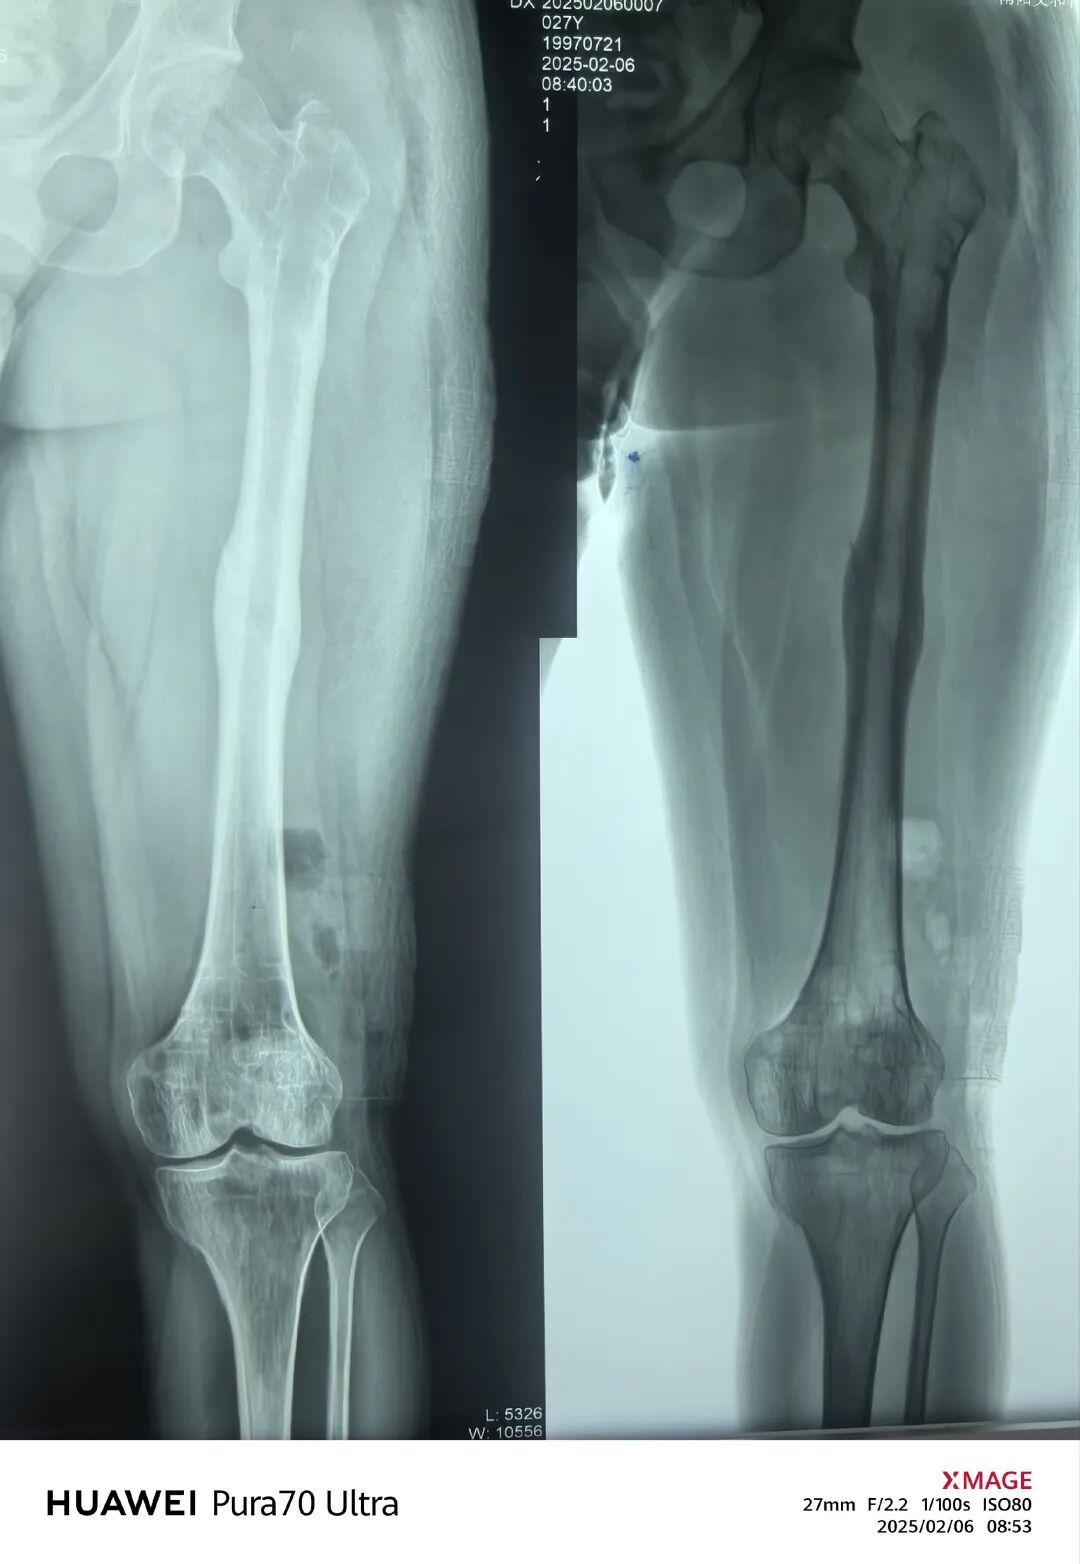

青年男性,股骨干骨折,切开复位,逆行髓内钉

初次手术疤痕如上图